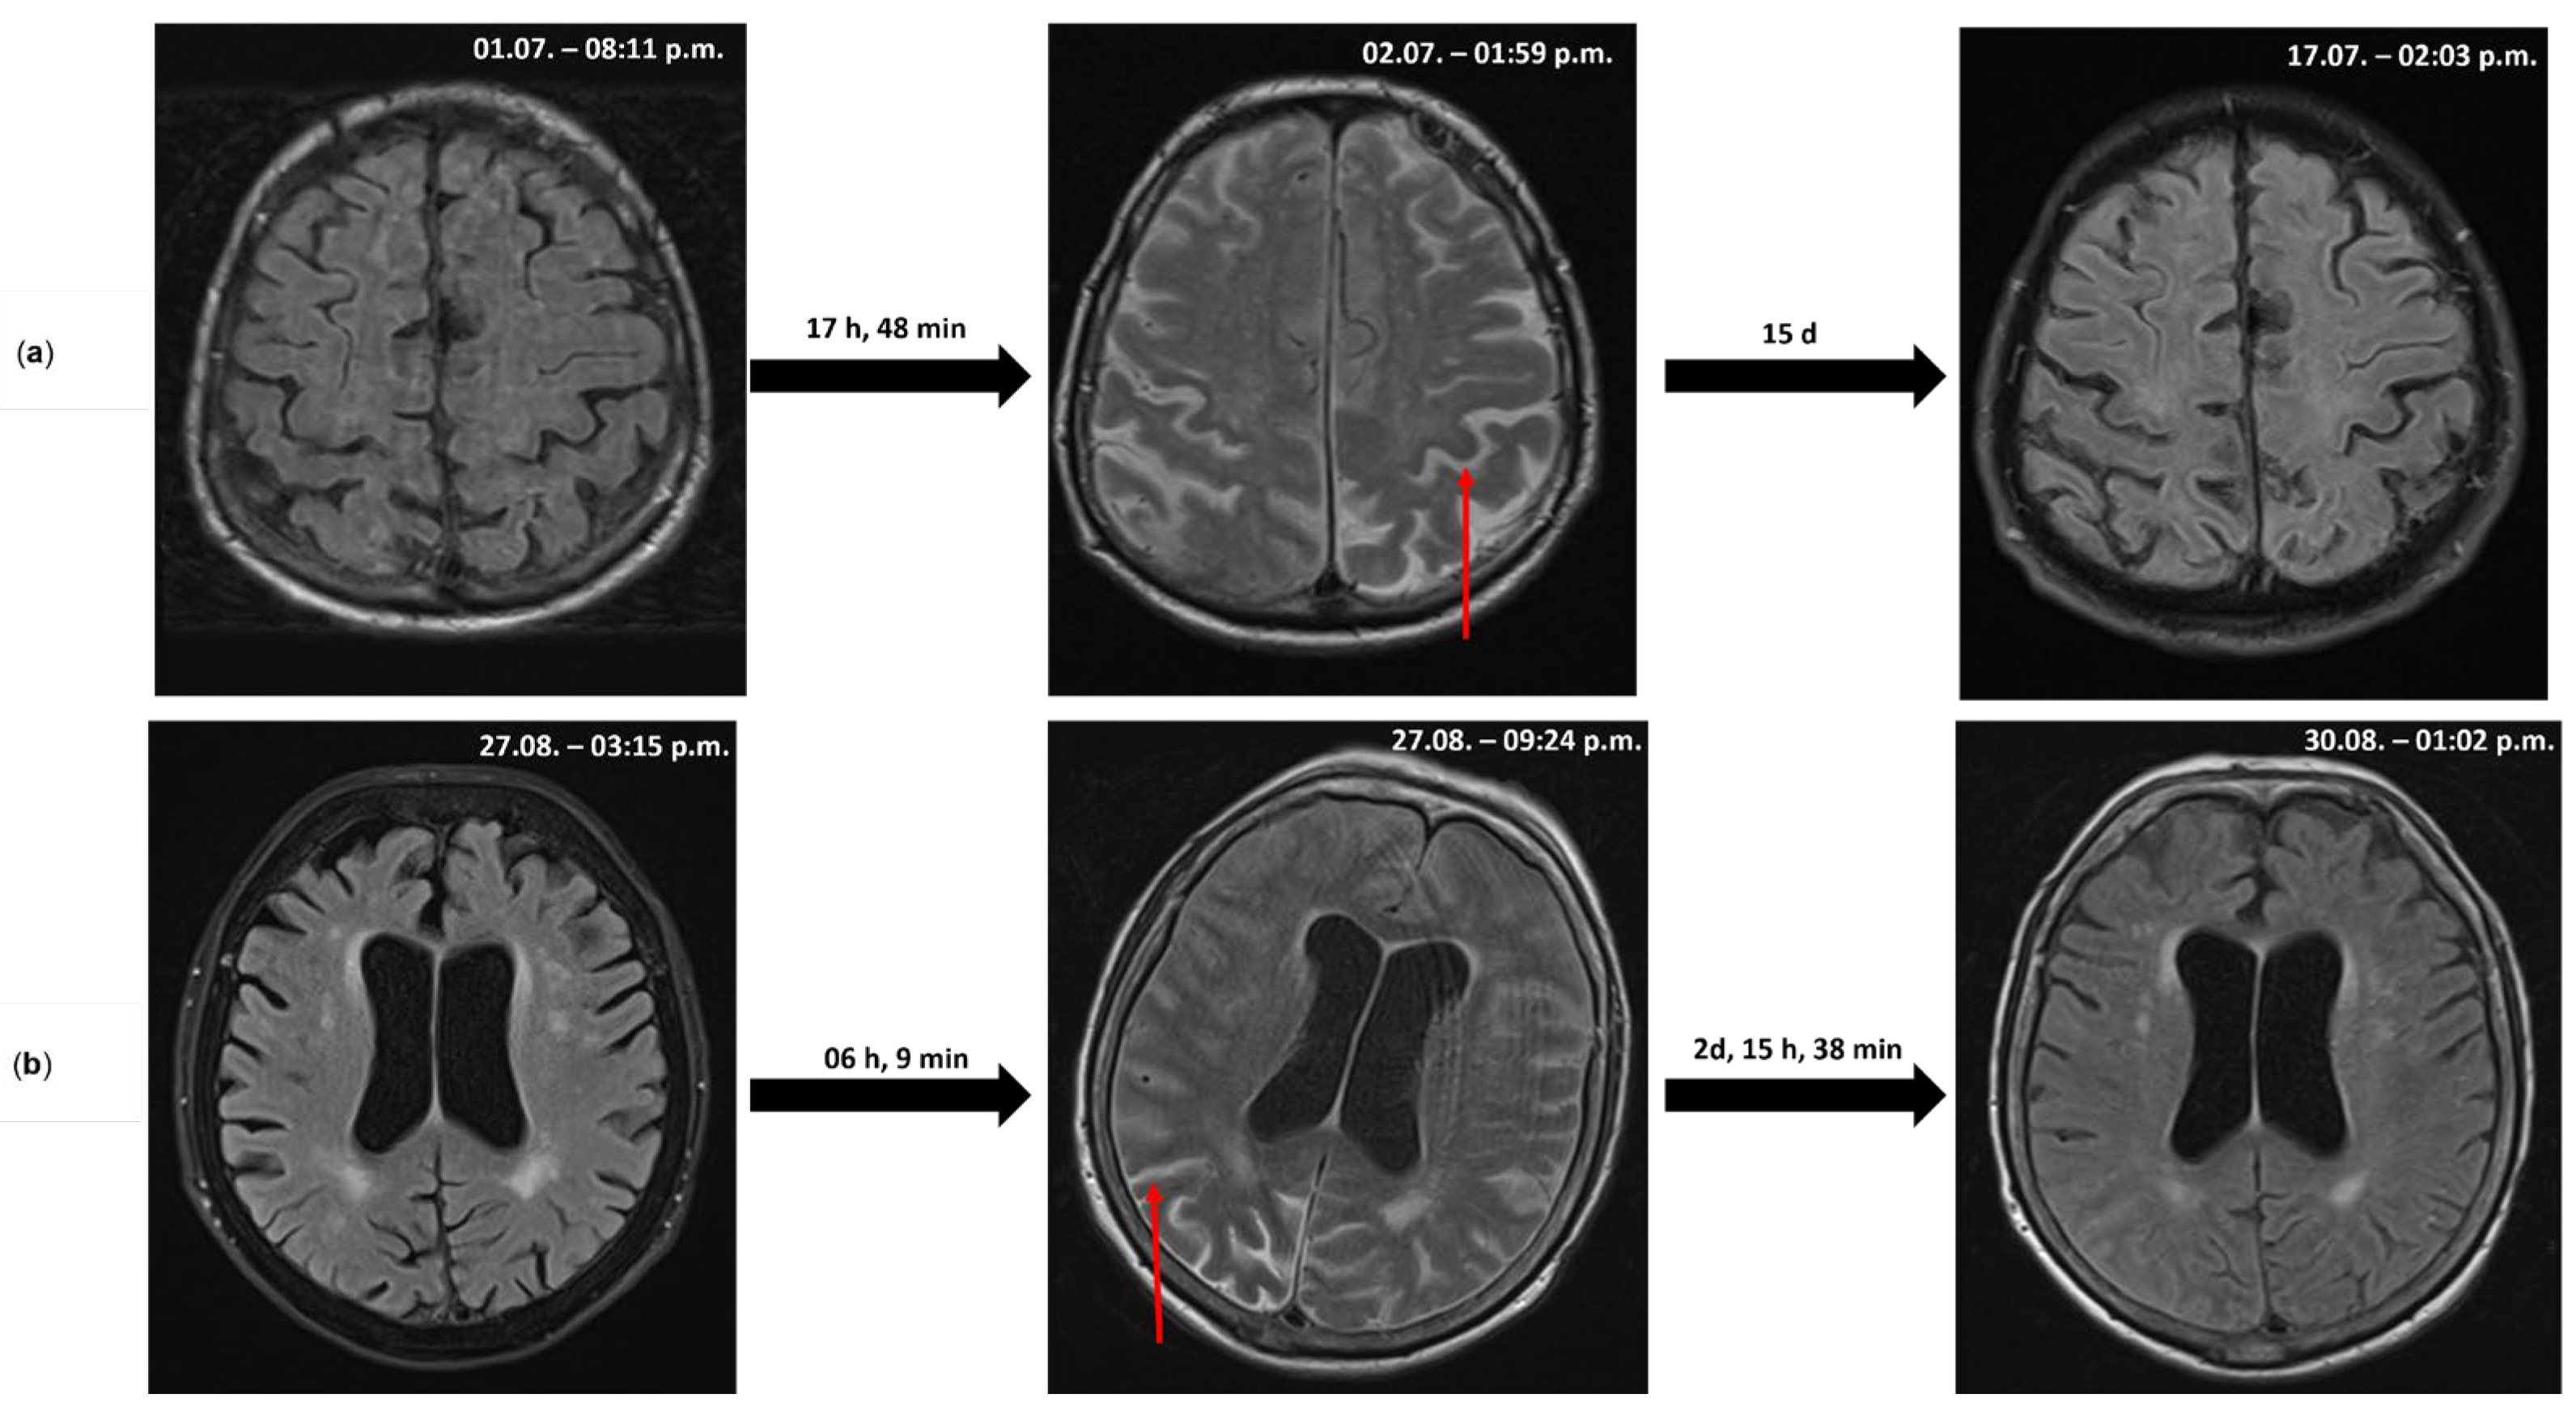

2.1. Case 1

2.2. Case 2